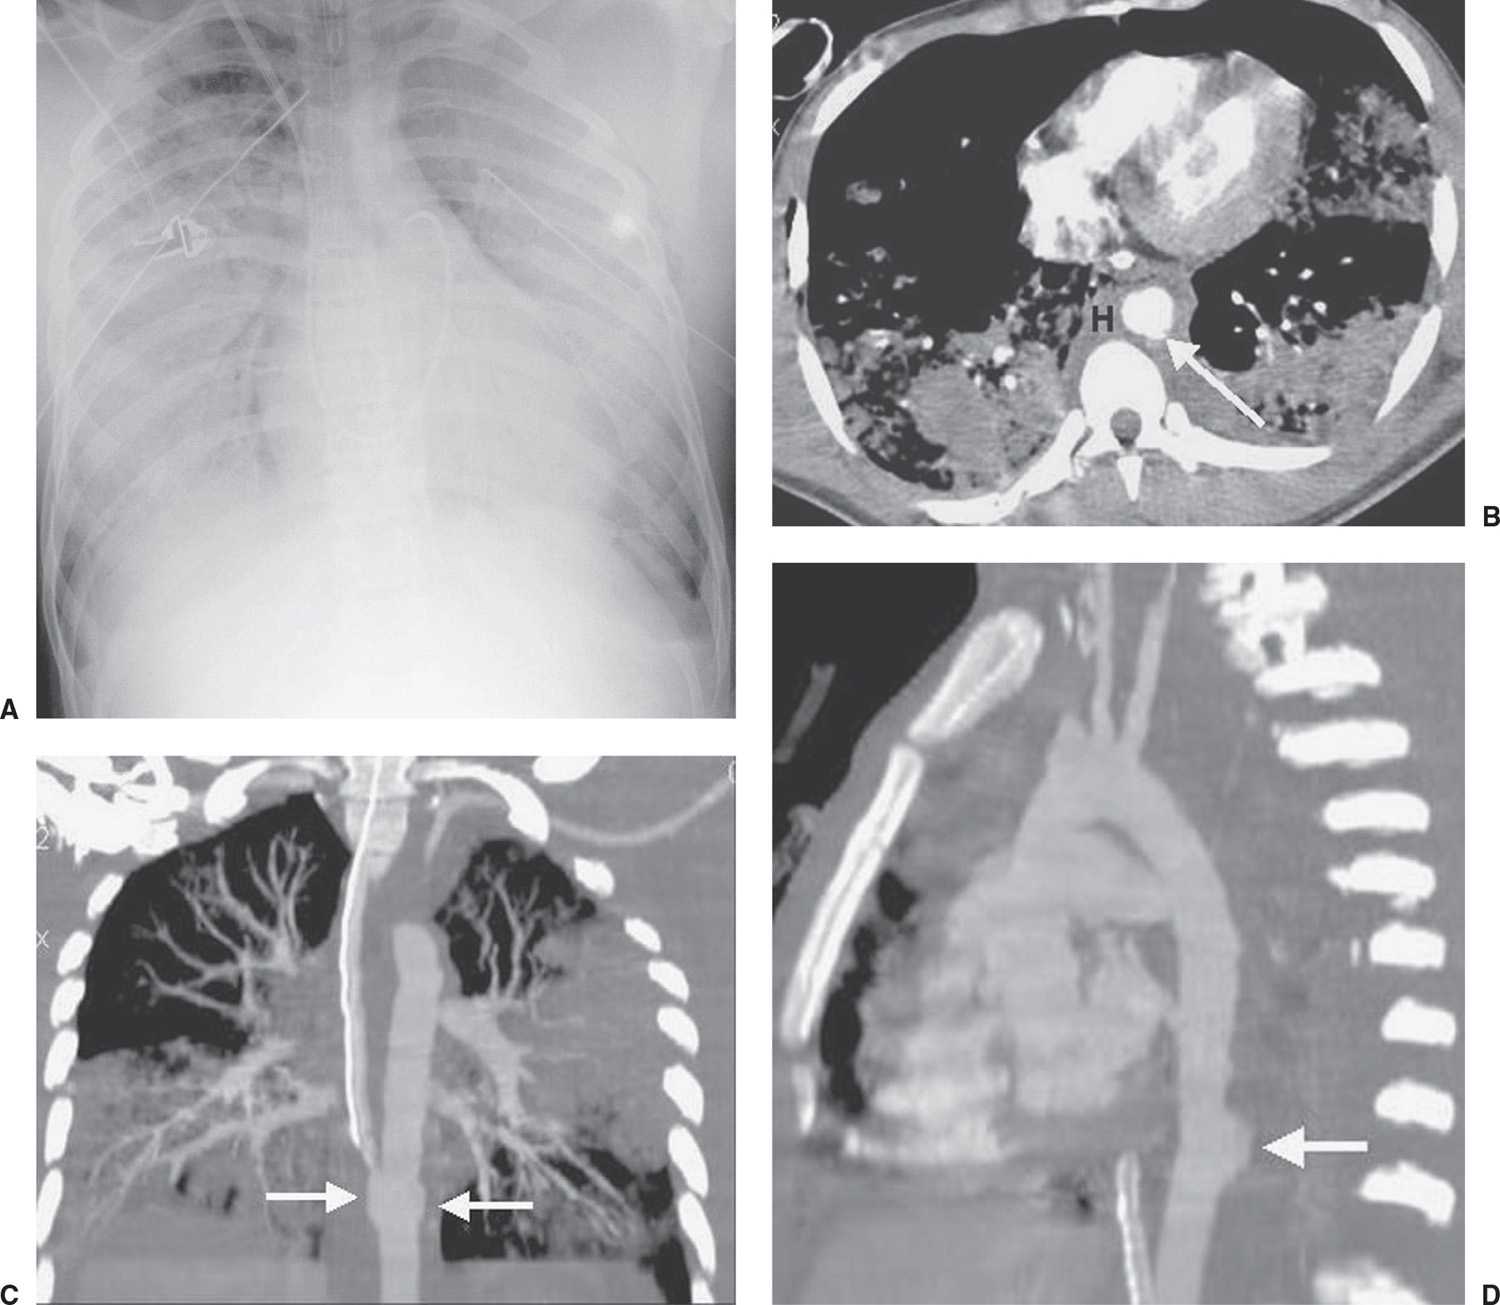

From radiologykey.com

Chest Trauma Radiology Key Meaning Of Chest Trauma This article focuses on chest trauma. Symptoms include pain, which usually worsens with breathing if the chest wall is injured, and sometimes shortness of breath. Hypotension or shock may be present. Chest trauma is a significant source of morbidity and mortality in the united states. Thoracic trauma is broadly categorized by mechanism into blunt or penetrating trauma. Mechanisms and patterns. Meaning Of Chest Trauma.

Chest Trauma Radiology Key Meaning Of Chest Trauma Common findings include chest tenderness, ecchymoses, and respiratory distress; This activity describes the cause,. Symptoms and signs of thoracic trauma. The chest can be injured by blunt force (such as in motor vehicle crashes, falls, or sports injuries) or by an object. Mechanisms and patterns of chest injury. Hypotension or shock may be present. This article focuses on chest trauma.. Meaning Of Chest Trauma.

From pubs.rsna.org

Imaging Manifestations of Chest Trauma RadioGraphics Meaning Of Chest Trauma The most common cause of blunt chest trauma is motor vehicle. Mechanisms and patterns of chest injury. Symptoms include pain, which usually worsens with breathing if the chest wall is injured, and sometimes shortness of breath. Symptoms and signs of thoracic trauma. Chest trauma is a significant source of morbidity and mortality in the united states. Chest injuries can be. Meaning Of Chest Trauma.

Imaging Manifestations of Chest Trauma RadioGraphics Meaning Of Chest Trauma Symptoms include pain, which usually worsens with breathing if the chest wall is injured, and sometimes shortness of breath. This activity describes the cause,. Thoracic trauma is broadly categorized by mechanism into blunt or penetrating trauma. Hypotension or shock may be present. The chest can be injured by blunt force (such as in motor vehicle crashes, falls, or sports injuries). Meaning Of Chest Trauma.